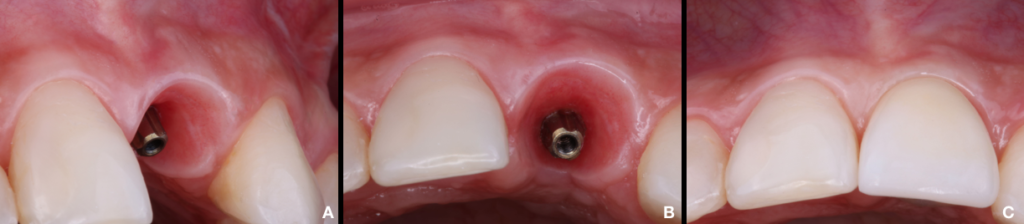

Criado essa zona de transferência (implate/perfil), selecionamos o abutment Ideale, mensurando a altura da cinta através do Túnel Check, onde na margem gengival marcava 4,5 foi subtraído 2mm para escolhermos uma cinta de 2,5mm, altura do munhão 4mm em relação ao espaço interoclusal e diâmetro de 3,3ø para dar a dimensão exata para acomodar todo tecido adjacente (Kan, 2003). Fig.8A/B

Sendo assim, instalado o componente definitivo (Ideale), o provisório foi adaptado sobre uma coifa de titânio e aparafusado na posição obedecendo todos os conceitos já citados. Para a confecção do dente definitivo, o provisório acoplado a um análogo, foi imerso em um silicone dentro de um pote dappen, adaptado o transferente, e acrescentado resina acrílica (Pattern Resin®) no perfil para copiar e transferir a posição do implante e os contornos da coroa em uma moldagem de moldeira fechada (Cardoso, 2005). Fig.9A/B/C

Contudo, após finalizado a coroa e baseado nas evidências clínicas e científicas, concluo que devemos obedecer a sequência correta do tratamento proposto, saber identificar a qualidade do tecido mole, indicar pilares que favoreçam a migração e acomodação do tecido e respeitar os limites de cada caso. Fig.10A/B/C